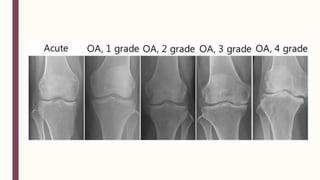

■ – – – – – ■ Martínez-Elizondo, P. Introduccióna la Reumatología. 5ta ed. México: Fondo editorial del Colegio Mexicano de Reumatología (2011)